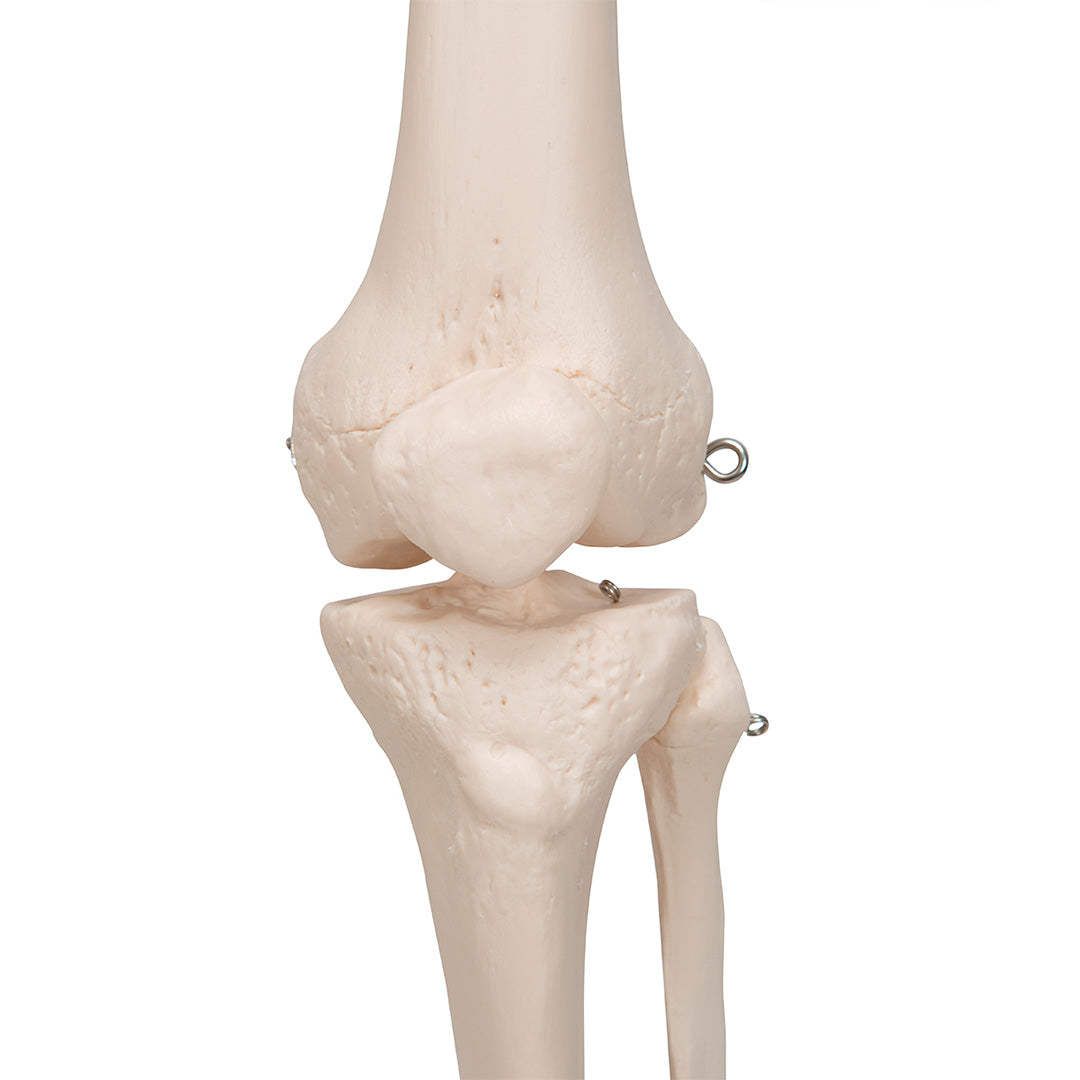

Calidad demostrada, postura aún más firme.

Stan, el modelo básico de esqueleto humano, es apreciado desde hace décadas en el mundo entero. Gracias a su excelente calidad y resistencia, es ideal para su uso en hospitales, colegios, universidades y laboratorios.

Decídase por un genuino Stan, el esqueleto artificial original

Características

Peso: 9.536 kg

Dimensión: 176.5 cm